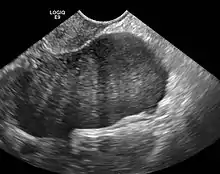

ovarian fibroma in ultrasound

Diagnosis is usually made by ultrasonography showing a solid ovarian lesion, or, on some occasions, mixed tumors with solid and cystic components.[1] Computed tomography and magnetic resonance imaging can also be used to diagnose fibromas. In a series of 16 patients, 5 (28%) showed elevated levels of CA-125.[1] Histopathology demonstrates spindle-shaped fibroblastic cells and abundant collagen.[3]